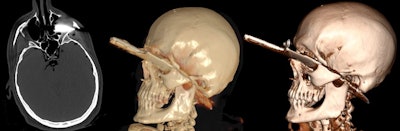

Between February 2016 and March 2019, Böven and her colleagues analyzed 112 fractures and injuries from 33 human cadavers (8 women, 25 men, with a mean age of 54 ± 18 years, range 31-92 years) that underwent whole-body postmortem CT after traumatic death. They reconstructed pathologies with CR and VR techniques, and classified fractures according to their dislocation.

Two forensic pathologists evaluated images according to their expressiveness and judicial relevance, and they decided whether CR reconstructions were suitable for judicial reviews. Two radiologists determined the detection rate of pathologies, and a traumatic cause of death was included.

CR was more expressive than VR for all three trauma categories (p < 0.01). Also, CR was more expressive than conventional CT when used for fractures with dislocation (p < 0.001), injuries of the ventral body surface (p < 0.001), and demonstration of foreign bodies (p = 0.033). CR and VR became more expressive with a higher grade of fracture dislocation (p < 0.001). In total, 20% of all pathologies in the CR and VR reconstructions were not detectable by radiologists.

"Due to the findings of our study, the use of CR for judicial reviews but also for other clinical demonstrations became the method of choice in our institute," Böven pointed out. "We also use CR reconstructions to demonstrate soft tissue injuries like stab wounds and penetration of foreign bodies more often than before."

- CR was more useful than conventional postmortem CT slices in cases of fractures with substantial dislocation, demonstration of foreign bodies, and body surface injuries not covered by other body parts or the CT table.